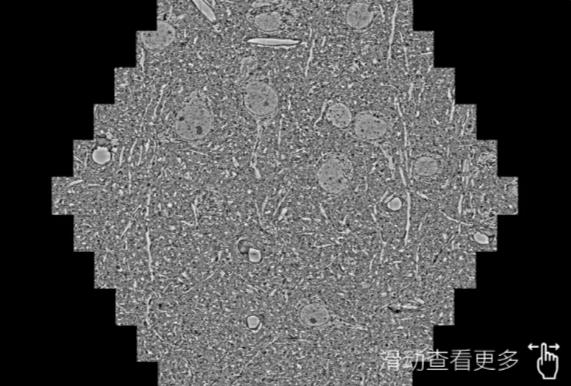

鼠脑切片。左图使用澄迈蔡司澄迈扫描电镜MultiSEM706对165μmx143pm面积区域成像,耗时仅需1.5秒。右图为鼠脑切片中30μm区域放大效果。样品由芝加哥大学B.Kasthuri提供。

使用蔡司高速澄迈扫描电镜MultiSEM对1mm²人脑皮层组织进行高分辨成像,并对其中的各种细胞结构进行三维重构分析。左图展示了2x3mm²组织平面中锥体神经元的三维重构效果。右图显示了局部体积神经元三维重构。图像由哈佛大学chtman实验室提供,渲染图由D. Berger 制作。